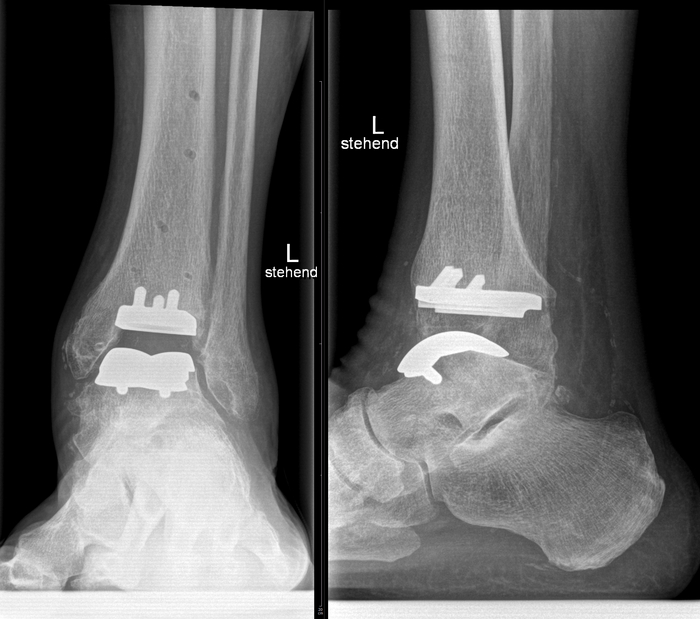

Начнём с нижних конечностей, где импланируют протезы:

- голеностопного сустава